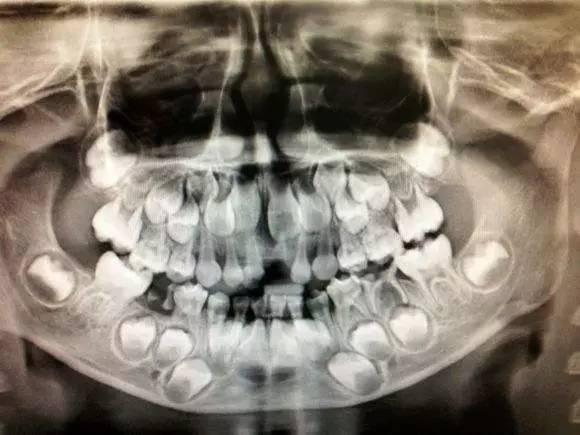

孩子换牙期间的x光片也太恐怖了!下颌骨里藏的全是牙齿,哈哈哈

原来换牙期的小朋友牙片是这个样子的所有牙都在萌发蠢蠢欲动

如上图,透过x光来看到换牙时期颌骨内的情况是这样的.

6岁左右少儿的乳牙和恒压的x光图,前面一排是乳牙,乳牙后面的是还没长

换牙期小朋友的牙片可以清楚看到有四排牙齿 (还有两颗是长在眼睛下方

全景牙科 x 射线八岁儿童的问题不松动他的乳牙-持续乳牙

用x光照射七岁男孩的牙齿